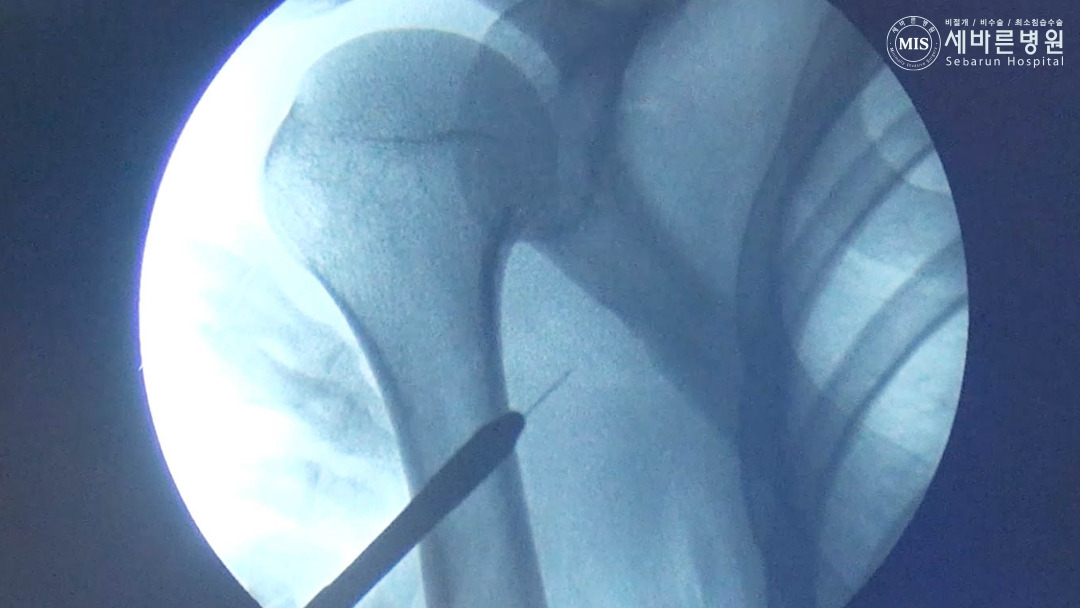

회전근개 내시경 단순 봉합술이 가능한 상황

회전근개 파열이 크지 않고, 부착부 근처에서 파열되어 딸려 올라가지 않은 경우라면 내시경을 이용하여 파열부위를 봉합합니다.

KakaoTalk_20240812_095352905_07.jpg

회전근개 내시경 단순 봉합술의 특징